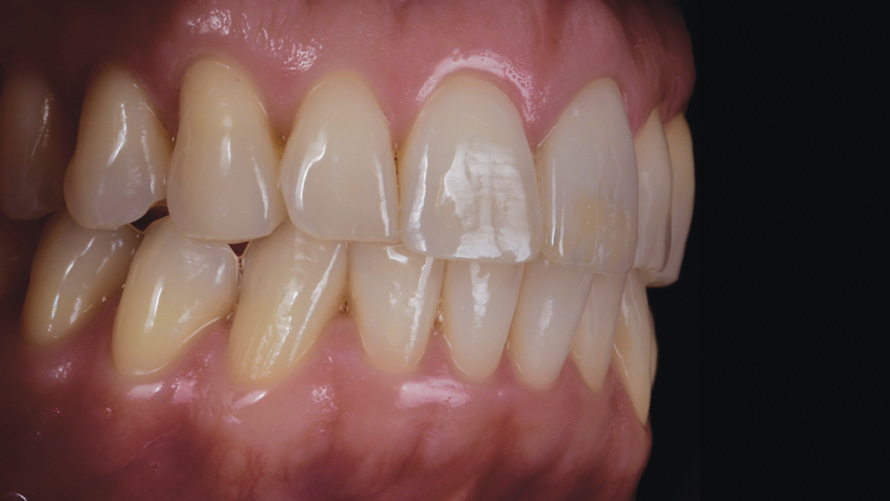

(14.) Case 1: Right- and left-side profile views of the definitive all-ceramic restoration on the maxillary right central incisor.

Figure 14

(15.) Case 1: Right- and left-side profile views of the definitive all-ceramic restoration on the maxillary right central incisor.

Figure 15

Eight weeks after the initial start of the walking bleach procedure, the final layered lithium disilicate crown was tried-in and evaluated for function and esthetics. Upon patient approval, the intaglio surface of the crown was etched for 20 seconds with a 9.6% hydrofluoric acid etchant, rinsed, and then scrubbed with a 37.5% orthophosphoric acid solution to clean out any ceramic debris. The crown was then placed into an ultrasonic bath of 91% isopropyl alcohol for 5 minutes, after which the intaglio surface was coated with silane and placed under a warm air dryer for 1 minute. A translucent self-adhesive resin cement was used to bond the final restoration to the preparation. The patients both stated that they approved of the form, function, and esthetics of the definitive restoration and that they were very pleased with the final results (Figure 13 through Figure 18). Routine periodic evaluations and radiographs were scheduled to monitor their oral health and esthetics.